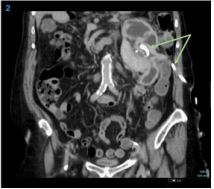

An 80-year-old woman with a history of metabolic syndrome, ischemic heart and cerebrovascular disease was admitted at the emergency department with asthenia and left abdominal and flank pain. She was on day 5th of empiric cefuroxime for urinary tract infection. On physical examination, the patient was febrile, but hemodynamically stable; an abdominal mass in the left flank was evident and painful on deep palpation; ipsilateral Murphy’s sign was present. Laboratory studies showed a marked elevation of C-reactive protein (329.9 mg/L), normal renal function, and mild isolated leukocyturia (70/μL) on urinalysis. A contrast-enhanced abdominal-pelvic computed tomography scan revealed an enlarged left kidney conditioned by a multiloculated cystic lesion (14 X 11 mm in the axial plane; 21 mm in the longitudinal plane), with homogeneous content and regular parietal thickening, associated to heterogeneous densification of the left perirenal fat, without hydronephrosis (Figure 1). In the absence of unequivocal findings of complicated cyst, the diagnosis of acute pyelonephritis with failure to cephalosporin therapy (no prior urine culture) was assumed, and piperacillin/tazobactam was started. However, since the patient maintained persistent fever and elevated inflammatory markers, the possibility of occult cyst infection was considered. Thus, a percutaneous approach was performed with immediate drainage of 1500 mL of purulent content. Multisensitive K. pneumoniae and E. coli were isolated in the cystic fluid, and the antibiotic spectrum was narrowed to cefuroxime, according to the antibiogram, and drainage of the cyst was maintained through a pigtail drain (Figure 2). She evolved favorably, having completed 1 month of antibiotic and subsequently referred to Urology consultation for a potential nephrectomy.

Figure 1: Contrast-enhanced computed tomography scans (coronal (a), sagittal (b) and axial (c) planes), showing a multi-septated cystic lesion in the left kidney with wall enhancement and water-like density content, without contact with the excretory system.